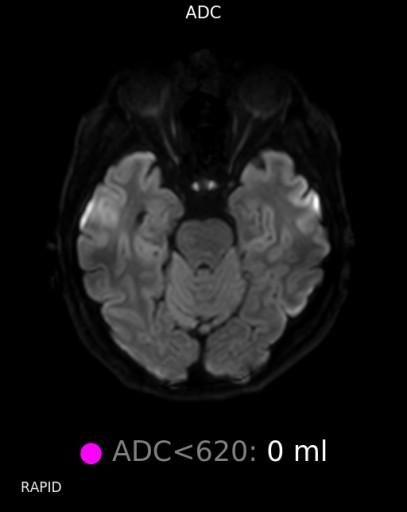

뇌 후두피질위축 봐주시면 감사하겠습니다(mri)

요즘 눈이랑 정신이 좀 이상해서 뇌mri를 찍었는데 이렇게 나오네요.

• 4번 째 사진

정확한 것은 정식 판독을 받아보아야 알 수 있겠습니다만, 개인적인 경험을 토대로 보았을 때에는 위축이 심하다고 보기에는 무리가 있어 보입니다. 뇌실이 비정상적으로 커져 보이지도 않고 뇌의 태두리가 두개골에서 많이 떨어져 있지도 않은 것이, 해당 사진들만 보아서는 위축이 심하고 치매를 의심하여야 한다 어떻다 판단을 내리기는 어려울 것으로 사료됩니다.

알츠하이머의 경우 뇌MRI로 진단하지는 않습니다.